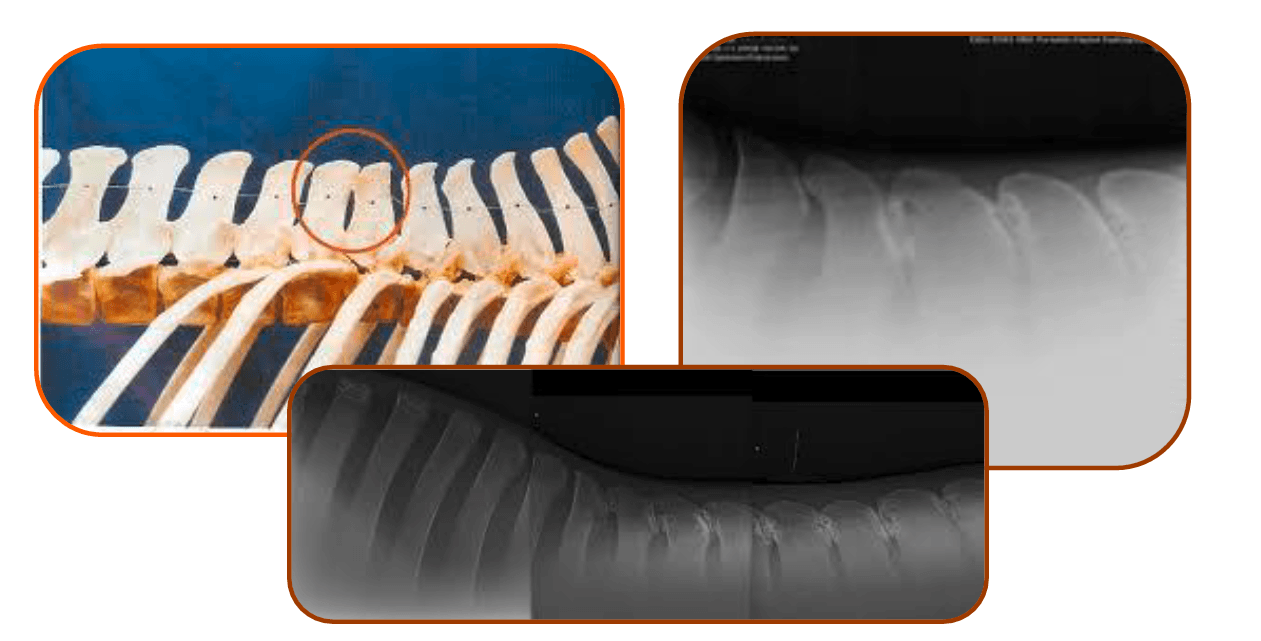

The x-rays below show no gaps in places, so every time this particular horse, has a rider's weight on those areas shown, are asked to turn on a circle or work or simply just carry a rider they probably will feel quite a bit of pain and therefore will show signs of that pain.

Ruling out Kissing Spines is very easy – A set of x-rays will give you the answer you need, but use an experienced vet who can

read the images well and who will understand that the vertebral bodies below the Kissing Spine area (called Facet Joints) also

need to be looked at to eliminate any doubt of pain from this part of the spine too.